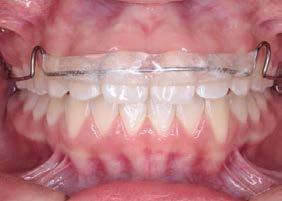

Introducción: La maloclusión clase II provoca proporciones irregulares en el perfil facial. Puede deberse a un maxilar adelantado y a incisivos superiores proinclinados y protruidos. Esta condición puede corregirse mediante el uso de aparatos ortopédicos en pacientes en crecimiento.

Objetivos: Conseguir clase I canina, controlar el crecimiento vertical, disminuir la convexidad esqueletal, reducir la sobremordida horizontal y mejorar el perfil facial. Caso clínico: Paciente femenina de 9 años, clase II esqueletal, biotipo dolicofacial, perfil convexo, clase II molar, clase II canina y proinclinación de incisivos superiores e inferiores. Resultados: Se logró clase I canina, se controló el crecimiento vertical, se redujo la convexidad esqueletal, se mejoró la sobremordida horizontal y el perfil facial. Conclusiones: El uso combinado de aparatos ortopédicos y aparatología fija en pacientes en crecimiento, junto con un diagnóstico y plan de tratamiento acertado, permite obtener resultados exitosos y estables en la corrección de estas maloclusiones.